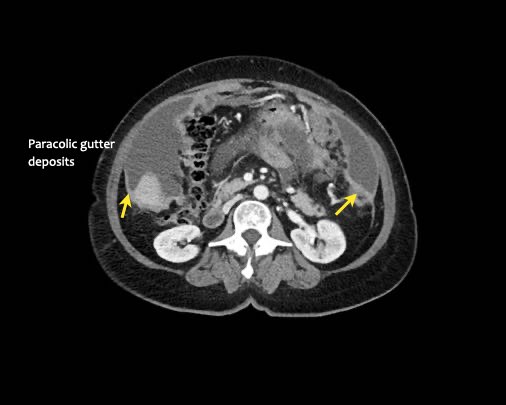

Rãnh cạnh đại tràng

Bất kỳ vị trí nào trong ổ bụng được phủ bởi phúc mạc đều có thể là đích đến của các nốt cấy ghép phúc mạc.

Các vị trí điển hình khác bao gồm rãnh cạnh đại tràng, túi cùng trực tràng-bàng quang hoặc trực tràng-tử cung, dây chằng liềm và mặt bụng của cơ hoành.